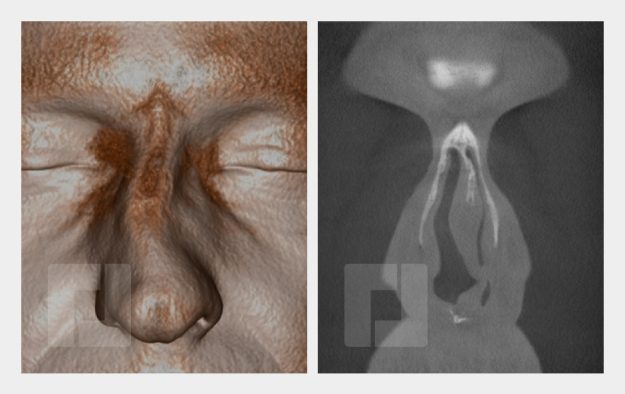

Beispiele

Durch Öffnen der Bildergalerie haben Sie die Möglichkeit selber durch die Beispiele zu navigieren.